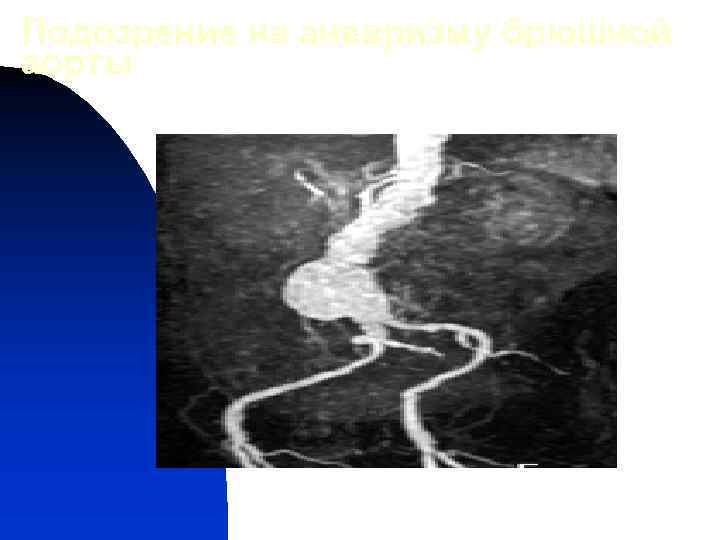

Подозрение на аневризму брюшной аорты УЗИ Аневризма Требуется уточнение РКТ с усилением или МРА Аортография (по показаниям)

Подозрение на аневризму брюшной аорты